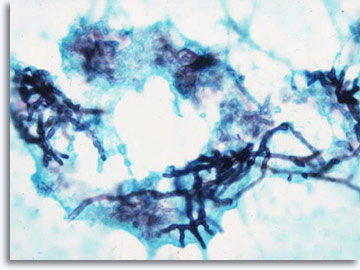

Als patroonherkenning niet onmiddellijk resulteert in een specifieke diagnose en categorie-indeling, kunnen aanvullende technieken zoals immuuncytochemie moleculaire informatie leveren die een bijdrage zal leveren voor de classificatie. Bij infectueuze processen is het mogelijk om specifieke etiologische infectie-agentia te isoleren, aantoonbaar met de Papanicolaou kleuring, Giemsma kleuringen voor bacteriën, en AFB kleuringen voor zuurvaste bacillen en PAS en GMS voor fungale organismen.

|